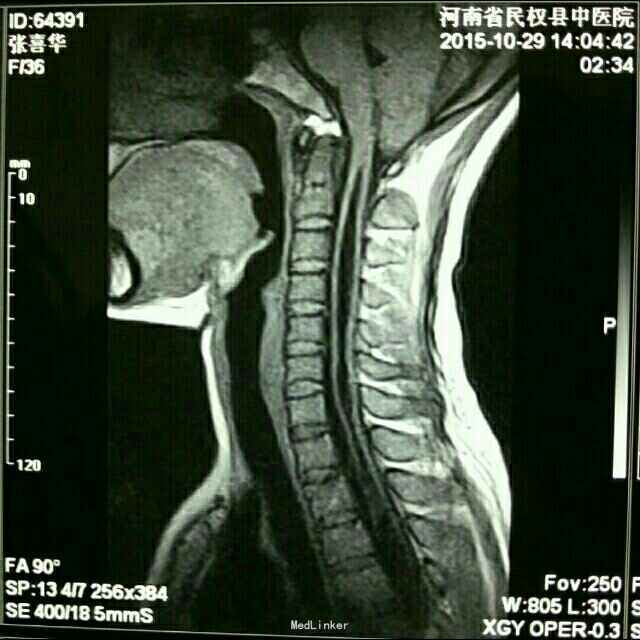

打开应用小脑扁桃体下疝并脊髓空洞症

小脑扁桃体下疝并脊髓空洞症

链接【小脑扁桃体下疝畸形】 又名阿诺德-奇阿(Arnold–Chiari)畸形,为常见的先天性发育异常。是由于胚胎发育异常使小脑扁桃体下部下降至枕骨大孔以下、颈椎管内,严重者部分延髓下段、四脑室下部下蚓部也下疝入椎管内。常合并有脊髓空洞,也可引起脑脊液循环受阻引起脑积水。小脑扁桃体下疝畸形常伴其他颅颈区畸形如脊髓脊膜膨出颈椎裂和小脑发育不全等。可表现为头痛、头面部上肢力弱、肩臂部痛温觉减退、吞咽困 难、眩晕、恶心、共济失调、甚至瘫痪等症状。 【治疗方法】

小脑扁桃体下疝畸形的主要治疗手段为手术治疗,手术的目的是为了解除枕骨大孔和上颈椎对小脑、脑干脊髓、第四脑室及该区其他神经结构的压迫,在可能的范围内分离枕大池正中孔和上颈髓的蛛网膜粘连,解除神经症状,缓解脑积水。 目前民权县中医院脑外科已在高倍显微镜下成功开展该手术![微笑][微笑][微笑]